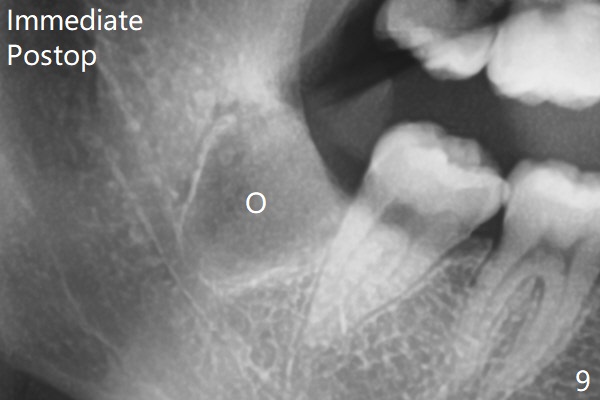

原来右下牙槽窝放置骨胶原塞(Osteogen Plug),而左下胶原塞。

塞的密度       Last     Next   智齿拔除